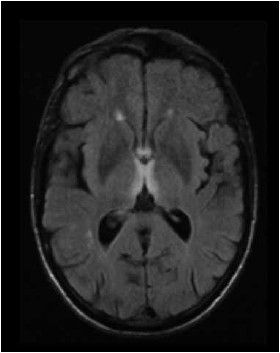

Paciente do sexo masculino, 12 anos, com quadro de diplopia, vertigem e dificuldade de marcha há 1 semana e, há 1 dia, evoluiu com sonolência. Tem diagnóstico de carcinoma de nasofaringe e perda de peso grave nos últimos meses. Ao exame físico, apresenta oftalmoparesia global e ataxia. Realizou o exame de imagem conforme mostrado a seguir. O líquor é normal.